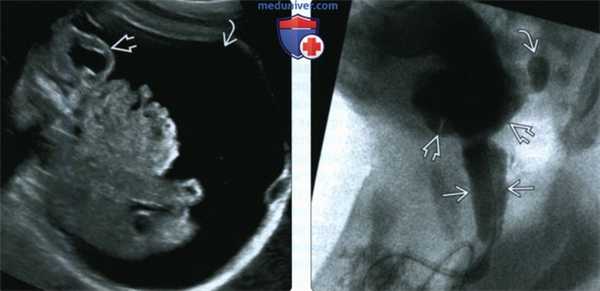

(Слева) Расширенная задняя уретра в основании расширенного мочевого пузыря напоминает по форме замочную скважину. КЗУ - наиболее частая причина обструкции нижних мочевых путей у плодов мужского пола.

(Справа) Фотография плода во II триместре. КЗУ. Перерастяжение мочевого пузыря привело к значительному увеличению живота. Грудная клетка малых размеров. Маловодие на раннем сроке приводит к фатальной гипоплазии легких.

(Слева) Предельное растяжение мочевого пузыря может привести к его разрыву с развитием массивного мочевого асцита, как в данном случае. Несмотря на частичную декомпрессию собирательной системы, аномальная форма почек сохраняется.

(Справа) МЦУГ у новорожденного с КЗУ. Выраженное расширение задней уретры Мочевой пузырь неправильной формы с трабекулами и дивертикулом возникшим под действием повышенного интравезикального давления.